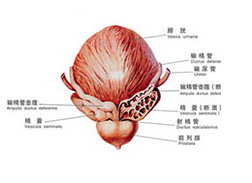

前列腺增生是“谁”引起的?

前列腺增生是谁引起的?前列腺增生疾病,是一种男性到了 中老年时期 容易发生的疾病。伴随着年龄的增长,疾病的发病率也呈上升趋势。前列腺增生严重危害着患者的身体。老年人...[详细]

【前列腺增生】

【前列腺增生】